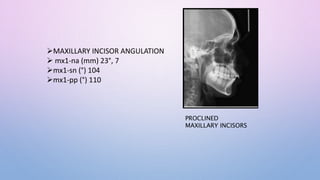

MAXILLARY INCISOR ANGULATION

 mx1-na (mm) 23°, 7

mx1-sn (°) 104

mx1-pp (°) 110

PROCLINED

MAXILLARY INCISORS